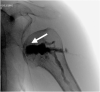

Osteonecrosis of the humeral head is an uncommon condition, and treatment options are controversial. The shoulder is the second most common location for osteonecrosis, typically presenting between the second and fifth decades of life. Early diagnosis and treatment are essential because osteonecrosis may progress and lead to significant pain and loss of function. Nonoperative options are limited and are based on addressing the cause of the osteonecrosis. Multiple surgical treatments have been described, and these techniques continue to evolve. Open core decompression of the humeral head has been found to be an effective surgical option to restore blood supply and stimulate new bone formation. The evolution of arthroscopic techniques combined with biological adjuncts allows a minimally invasive approach with potential to accelerate revascularization and bone growth. We describe our technique for arthroscopic-assisted intraosseous bioplasty of the humeral head for the treatment of osteonecrosis.